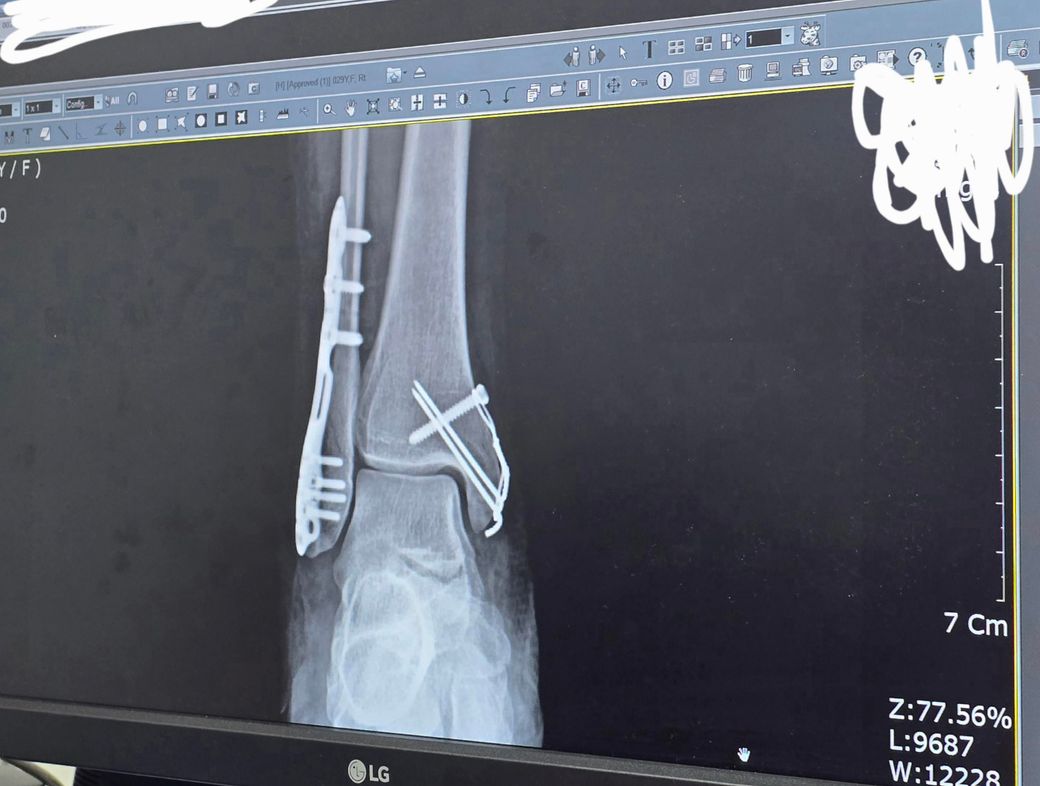

3/15일 발목 골절 후, 복숭아뼈쪽 3군데 골절로 수술을 꼭 해야한다는 안내를 받아 3/19일 수술을 하였습니다.

수술 후 엑스레이를 찍은 사진입니다.

• 1번 째 사진